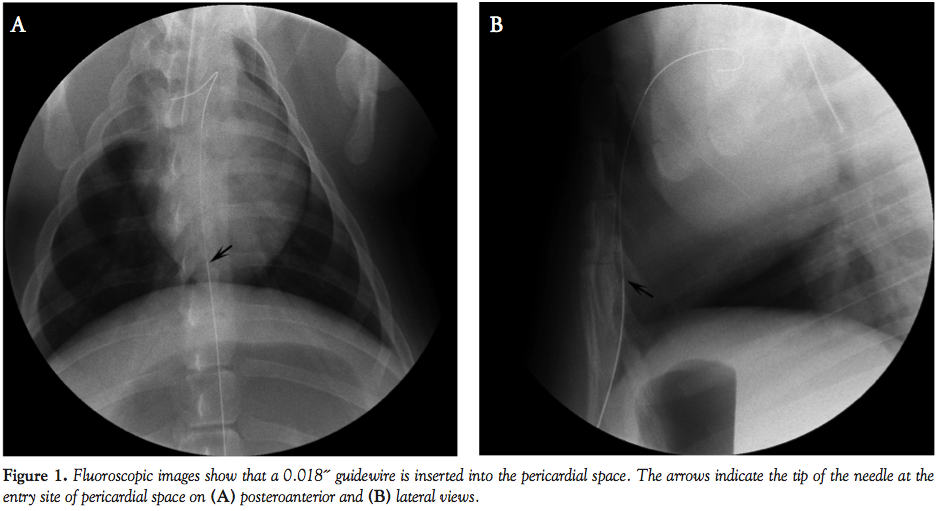

Next a 0.035˝, Rosen heavy-duty guidewire (William Cook Europe) was used to exchange the dilator of micropuncture set with a 7 Fr introducer sheath (Radifocus, Terumo Corporation). Through the introducer sheath, a 0.016˝ guidewire (Radifocus) was inserted into the pericardial space. The guidewire was looped superiorly and then inferiorly around the heart until the nearby region of the apex. Then a 6.4 Fr user attachable silicone catheter from a vascular access port set (ImPort, Medtronic, Inc) was placed over the guidewire to the guidewire tip. The guidewire and the sheath were removed, leaving the silicone catheter in place. A subcutaneous tunnel was established from the subxiphoid skin entry site to the left subaxillary area. The silicone catheter was placed through the tunnel and connected to a low profile port. A small incision was made and a subcutaneous pocket was created with blunt dissection. The port connected to the silicone catheter was placed in the pocket (Figure 2). The skin was closed. Fluoroscopy was performed when 5 mL of diluted contrast medium with saline solution was injected through the subcutaneous port to document the subcutaneous course and intrapericardial location of the silicone tube (Figure 3). The contrast medium injected into the pericardial space was immediately drained from the port. The color of contrast medium drained from the port was inspected to exclude the potential hemopericardium as a procedure-related complication. Chest fluoroscopy was also performed to check for occurrence of the pneumothorax.